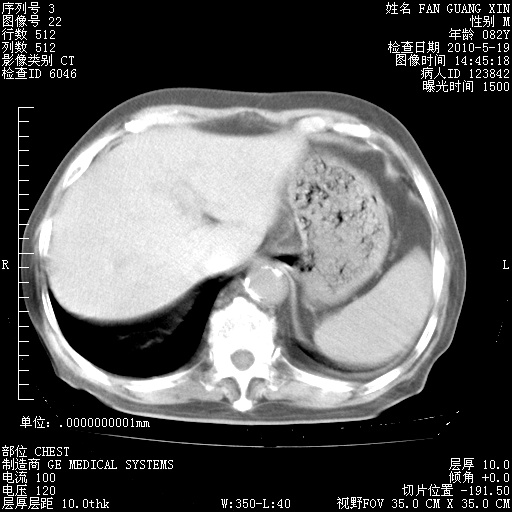

还需要哪些辅助检查?我们医院排除真菌感染没有任何检验方法,胸片好像能够排除肺部真菌感染。